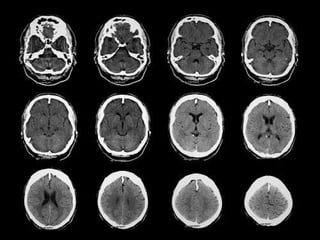

This document provides guidance on interpreting a basic computed tomography (CT) scan of the brain. It outlines a systematic approach by comparing left and right sides, looking for midline shifts, and reviewing cross-sectional anatomy at each slide. Key anatomical landmarks are identified, including gray matter, white matter, ventricles, cisterns, sulci and fissures. Specific pathologies like subdural hematomas and physiologic calcifications are also addressed.